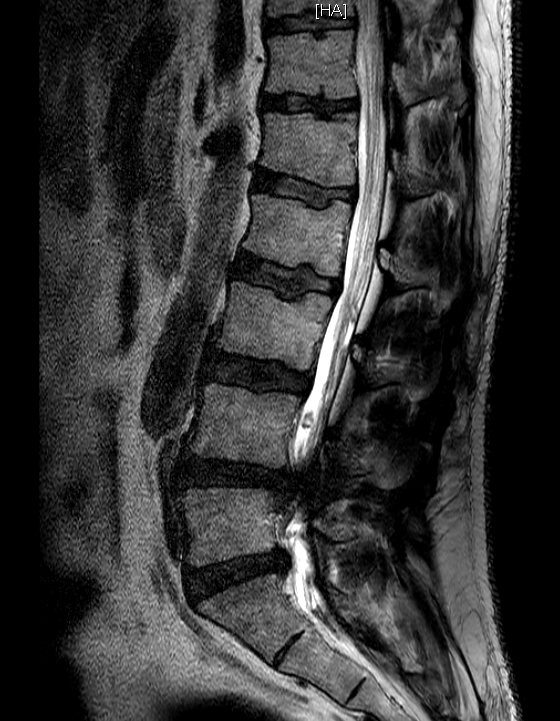

| Subject | 척추협착증 관련 질문 드립니다. |

https://www.redtea.kr/pb/pb.php?id=qna&no=7662 엊그제 글을 한 번 올렸는데 다시 올리는 이유는 MRI 사진을 환자인 가족에게 파일로 받았기 때문에 더 정확한 설명을 들은 수 있지 않을까라서 입니다. 다른 병원에서 진료만 받아보려고 토요일에 가서 파일을 받았다네요. 이미 한 번 질문을 드렸고 많은 조언을 받았기 때문에 다시 올리는 게 겸연쩍기도 하고 한 달 간 다른 병원 몇 군데를 가볼 예정이지만 그래도 하나라도 많은 조언을 듣고 싶어서요. 진단을 해주신 대학병원 의사선생님을 못 믿는 건 아닌데 앞서 글에서도 설명드렸듯이 한 달 간 휴직을 하는 것에 대해서나 당뇨나 다른 병들 때문에 수술보다 다른 시술이나 치료가 좋지 않을까 싶어서 입니다. 물론, 여러 의사선생님들이 수술하라고 하시면 예정대로 빠르게 수술할 생각이고요. 사진은 측면 4장 단면(?) 3장 정도 있는데 잘 몰라서 우선 2장만 올려봤습니다. 같은 내용으로 번거롭게 두번이나 글 올려서 홍차넷 여러분께 죄송합니다. 0